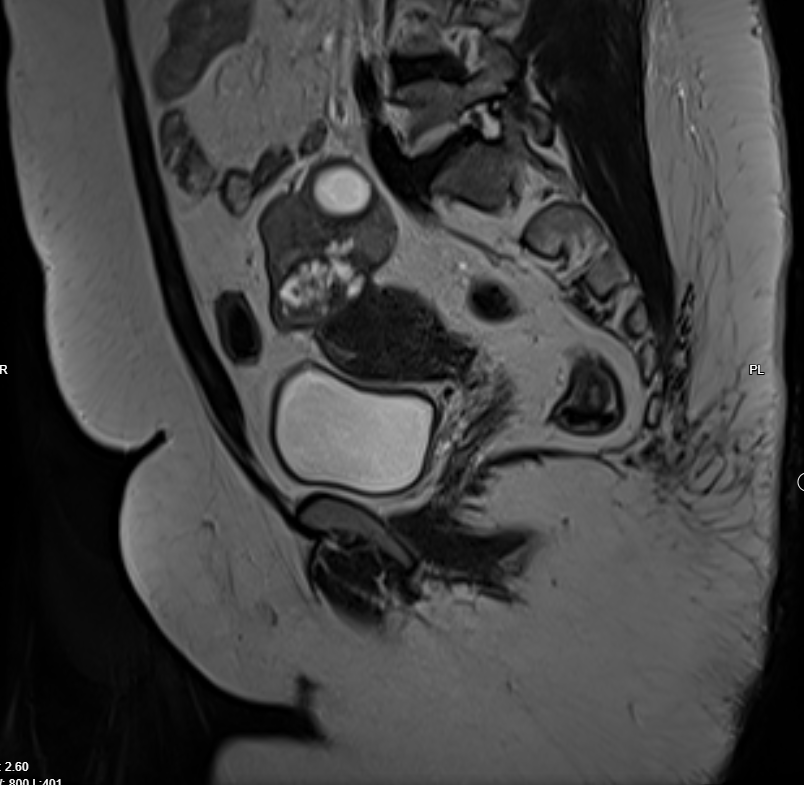

Pelvic MRI with IV contrast

· Evidence of left adnexal irregular lobulated shape solid mass replacing most of left ovarian parenchyma , T1 iso intense , T2 hypo intense , restricted in DWI, no fat , no calcification , after giving contrast showing diffuse progressive hyper enhancement , with high risk curve of enhancement , these radiological features highly suspicious for malignant ovarian tumor, O-RADS 5.